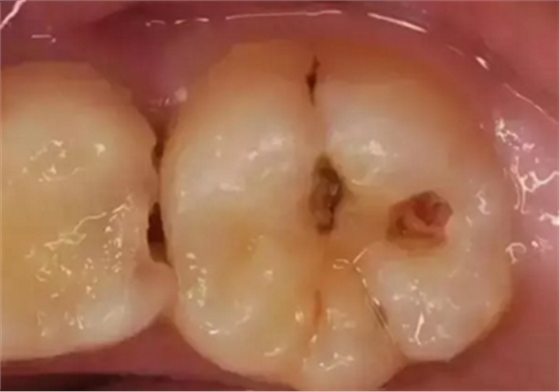

蛀牙從外表看就表現(xiàn)為一個黑點,通常位于窩溝點隙(牙面上點狀或線狀凹陷)

淺齲——侵犯牙釉質(zhì):起初的蛀牙只限于牙齒表面淺層,牙面上會出現(xiàn)一個小黑點,不痛不癢,所以很容易被我們忽視。

中齲——感染牙本質(zhì)表層:到這個階段,已經(jīng)能看到明顯的蛀洞,此時的病變位于牙本質(zhì)的淺層,牙齒會冷熱酸甜敏感,但是離開刺激物就沒有不適感。

深齲——滲透牙本質(zhì)深層接近牙髓:此時的病變已經(jīng)發(fā)展到牙本質(zhì)深層接近牙髓了,有明顯的蛀洞且較深,伴隨明顯的牙痛,遇到外界刺激痛感加重,牙齒變得很敏感,還會出現(xiàn)食物鑲嵌在牙洞的情況。